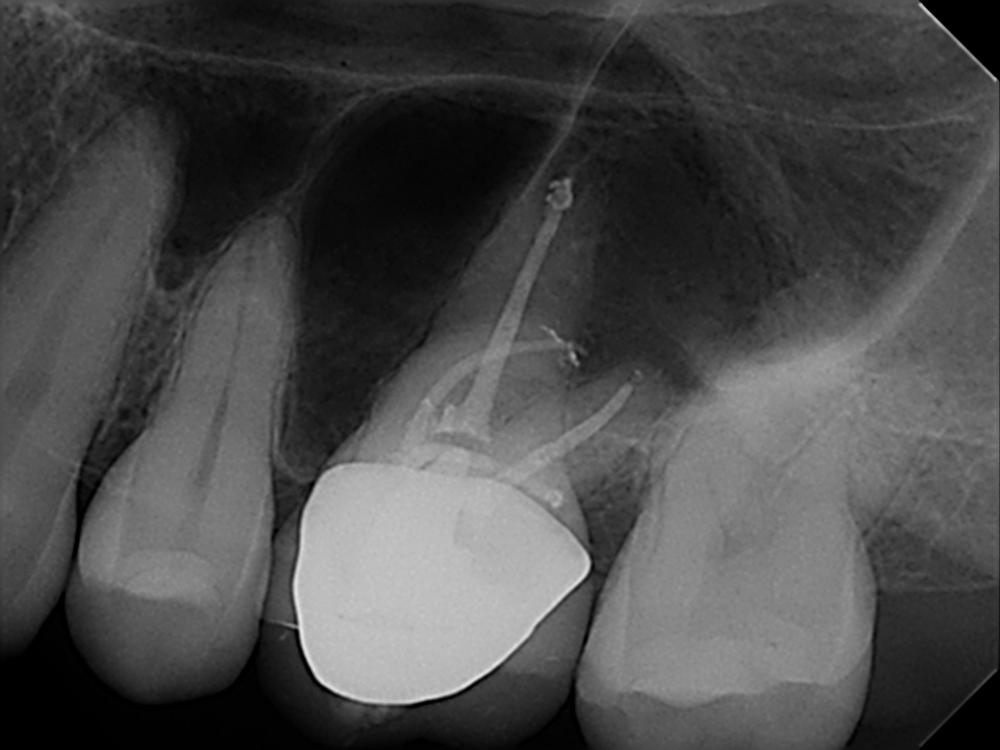

I’m an endodontist from Atlanta, Georgia, and I did my specialty at the University of Pennsylvania, graduated 2013 and I wanted to share with you this case of a molar number 14 of a 33 year old patient with irreversible pulpitis and Symptomatic Apical Periodontitis. This case was diagnosed and accessed through the crown using diamond burrs. Then, irrigation with sodium hypochlorite.

“When you see a case like this, you’re wondering to yourself, what file am I going to use for this? How am I going to negotiate that canal without having file breakage?”

First, I tried to get patency of the canals, I did the patency of the distal mesiobuccal canal and distal canal using 10 files, and then worked my way up to a 15 file. I instrumented this case using an SX file to open the orifices, then used copious irrigation with sodium hypochlorite.

I started using the EdgeEndo files utilizing crown down technique, when you see these type of canals that are very curved, you want to flare up a little bit the upper portion of the canal, so your files can slide down easier and have less binding on the walls. I started doing the crown down from a 40 to a 25 and then went all the way to 40’s on the mesiobuccal, on the distal, and I did the palatal to a 45.

I went to a 40 on that root… any other file would have just broken and just could have been impossible to retrieve.

When I took the x-ray to see how the cones were fitting, I noticed that there was a canal missing, so I used the CBCT to find the MB2 canal. All this, of course, while I’m using my EdgeFiles, I used also lube, RC prep for the instrumentation, and I also used a lot of sodium hypochlorite to instrument. Before doing the cone fit, I do irrigation with ultrasonics using sodium hypochlorite , EDTA, and chlorhexidine. I did my cone fit with the Edge Gutta Percha and the AH Plus sealant.

When I took the x-ray to see how the cones were fitting, I noticed that there was a canal missing…

Now, I can tell you when I took the x-ray I saw that the MB2 was missing, so I took a CT scan and noticed the MB2 and noticed the weird unusual buccal inclination of the MB2 to the palate, and the MB really pointing towards the buccal. It looked almost like a snake tongue. I was like, oh wow, this has been the thing that I was looking for. I found the MB2 on the second visit. I closed everything up before that with calcium hydroxide, then on the second visit I found MB2.

I proceeded to do the instrumentation up to a 35 on MB2 with the same sequence, using sodium hypochlorite, first of all going up to a number size 15 and doing crown down to a 35. After that, I irrigated everything with sodium hypochlorite, EDTA, chlorhexidine, and I dried everything up with sterile paper points, and took an x-ray with the cone fitting, with cones and age plus sealant.

After verifying that the diagnostic intermediate x-ray looks fine, I closed everything up using vertical condensation, just leaving 4 millimeters of the apical portion of the cone, and then back filling with Edge Gutta Percha. After that, very important, I always put an orifice barrier. I use purple permaflow orifice barrier, then I put a cotton pellet and that was that.

I was trained at U Penn and we believe in large apical sizes and I went to a 40 on that root… any other file would have just broken and just could have been impossible to retrieve. When I did this case I was like “AAAAAAH the panacea.”